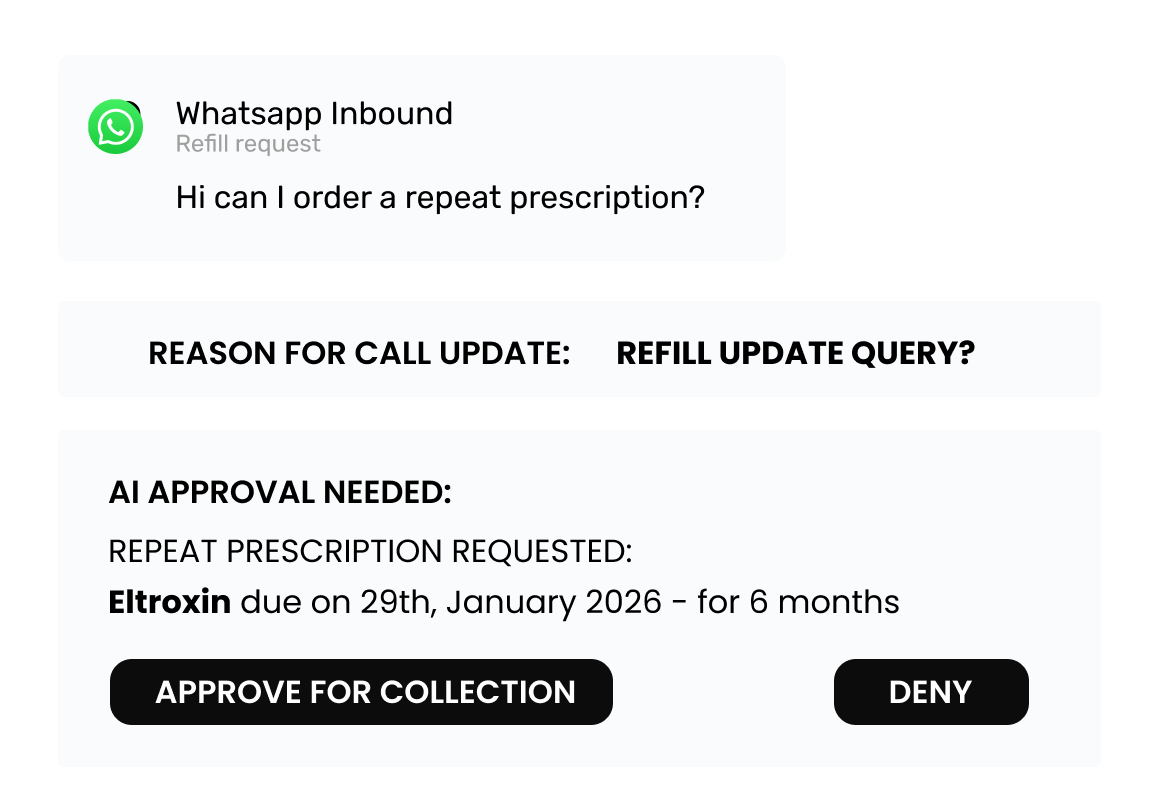

WhatsApp Messaging

Patient notifications, reminders, two-way chat

Unified Inbox

All calls, messages, and tasks in one dashboard